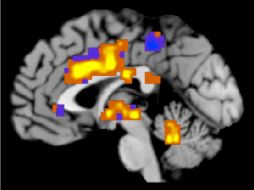

Tecnología Para el cerebro la música es tan importante como el romance 28 de mayo de 2013 - 19:42 hs Ciencia Música